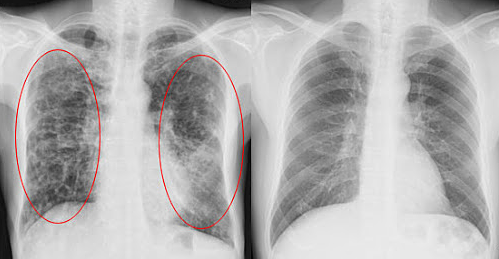

CUF清肺糖上市前,经过了东京医科大学严格的临床试验:

1000名肺部感染者服用CUF清肺糖一个月,

肺部杂质几乎全部消失,效果非常接近洗肺。